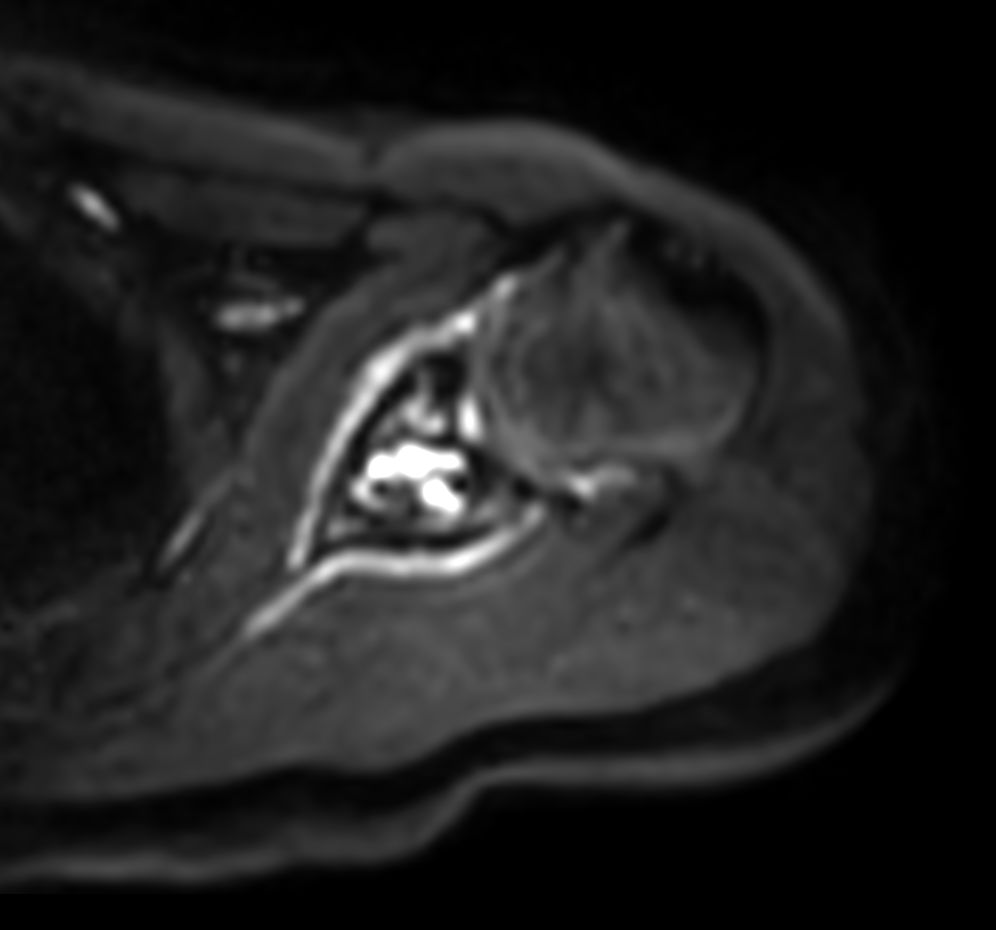

Patient with a shoulder tumor. Compressed SENSE acceleration is included to speed up sequences while maintaining equal image quality. mDIXON XD TSE in included (pre- and post-gadolinium injection) providing uniform, complete and consistent fat-free imaging. Besides the regular DWI EPI, a high resolution diffusion method is also included.

Axial DWI EPI (b500)

Axial DWI EPI (b1000)

Axial DWI EPI (ADC)

Axial DWI EPI (b500) - High resolution

Axial DWI EPI (b1000) - High resolution

Axial DWI EPI (ADC) - High resolution